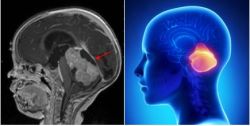

- Chẩn đoán xác định dựa vào các phim chụp cắt lớp vi tính hoặc cộng hưởng từ.

- Các phim cộng hưởng từ có tiêm thuốc đối quang từ được coi là phương tiện chẩn đoán chính xác nhất đối với u dây thần kinh VIII.

- U thường có đặc điểm hình tròn bầu hình bầu dục nằm ở ống tai trong lan vào vùng góc cầu tiểu gây chèn ép cầu não và tiểu não. Mật độ u có thể thuần nhất, hoặc dạng nang và đặc xen kẽ.

- Phim chụp cắt lớp vi tính giúp khảo sát những thay đổi vùng ống tai trong liên quan đến tế bào xoang chũm, trên cơ sở đó giúp hoạch định kế hoạch mổ, đặc biệt là mổ theo đường xuyên mê nhĩ.